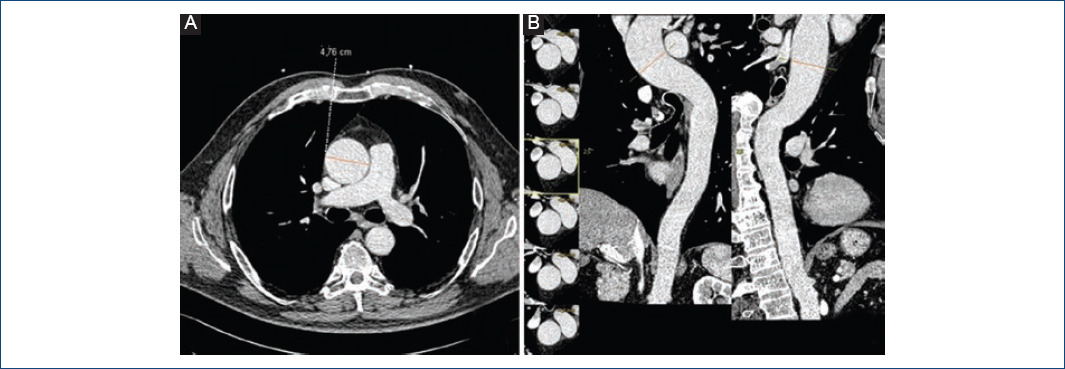

La asociación más frecuente es con dilatación y aneurismas en la aorta torácica, por lo que en algunas publicaciones actuales las engloban dentro del mismo síndrome (Fig. 4). Está demostrado que los pacientes con VAB, en comparación con los que presentan VAT, tienen mayor riesgo de desarrollar dilatación de aorta ascendente y disección aórtica5,15. Sin embargo, los datos sobre la prevalencia de la asociación son variables (33-80% de los casos de VAB), quizá debido, aparte de a la propia heterogeneidad de la enfermedad, a la falta de consenso en los estudios sobre las medidas para definir dilatación, las técnicas de imagen usadas, la región de la aorta considerada, etc. Existe discordancia acerca de si el distinto morfotipo valvular bicúspide es o no un predictor de mayor riesgo de dilatación aórtica23,29. La etiología y la patogénesis de la dilatación aórtica en los pacientes con VAB es incierta hasta la fecha, pero se plantean dos teorías. Hay autores que abogan por la hipótesis hemodinámica-mecánica. El estrés mecánico sobre la pared aórtica ha sido estudiado mediante el análisis de los flujos por RM cuatridimensional. Debido a la apertura anómala de la VAB se forma un flujo excéntrico dirigido contra la pared aórtica, y sería esta fuerza tangencial constante la que termina por generar la dilatación29,30. Otros autores apoyan la hipótesis genética, que postula que existen unas alteraciones genéticas comunes al riesgo de desarrollo de aneurismas aórticos y a la aparición de VAB. El hecho de que la aortopatía se haya demostrado más frecuente en familiares de primer grado de individuos con VAB apoya esta teoría21. También es conocida la estrecha relación en el desarrollo embrionario entre las válvulas semilunares y el remodelado de la raíz de la aorta y la aorta ascendente; y a su vez, está demostrada la participación de las células de la cresta neural tanto en el desarrollo valvular como en el desarrollo de la pared aórtica31. Como resultado de ello, las alteraciones en las señales intracelulares e intercelulares podrían justificar la coexistencia de ambas patologías.

Figura 4 Tomografía computarizada de aorta. A: plano axial a nivel de los grandes vasos que muestra una dilatación importante de la aorta ascendente torácica (4.76 mm). B: reconstrucciones oblicuas de la aorta en las que se observa la dilatación de la aorta ascendente.